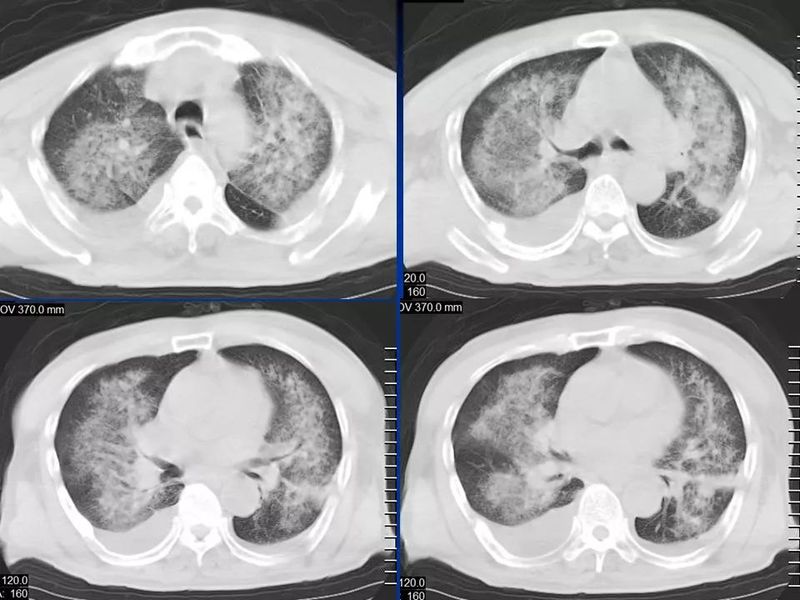

主任提醒:这个病很容易误诊为肺炎!